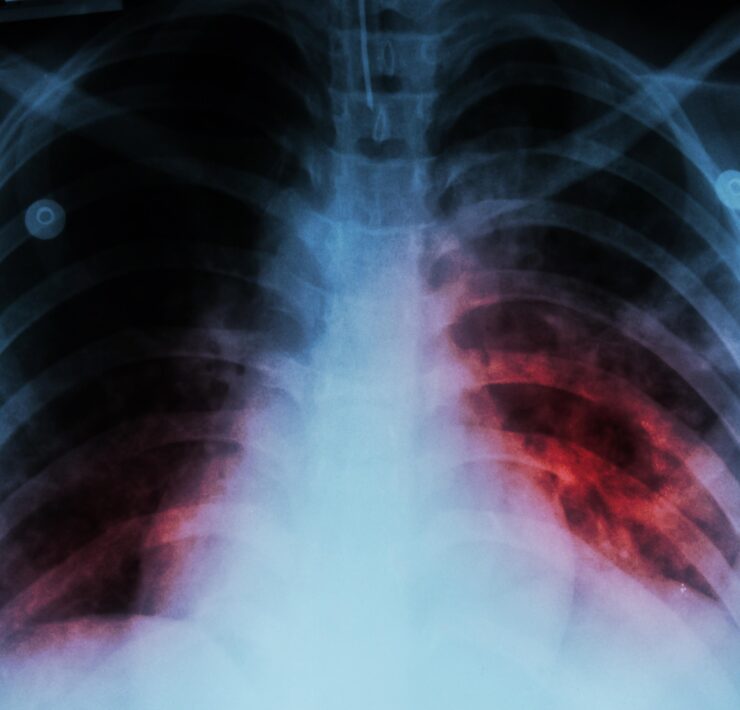

Ciudad del Carmen, Camp.__ Pocos casos de tuberculosis en el estado de Campeche; de acuerdo con la Secretaría de Salud a nivel nacional, en el 2022, se registraron 28 mil casos de tuberculosis (TB), por lo tanto en el estado de Campeche, es mínima la incidencia, La tuberculosis es una bacteria que suele afectar a los pulmones, se propaga por el aire cuando una persona infectada tose, estornuda o escupe, dijo el presidente de la Asociación de Médicos Egresados de la Universidad Veracruzana, AC, Froilán Palestino Cruz.